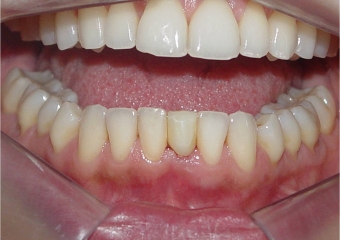

Imagens do dente provisório fixo imediato, no implante Cone Morse Facility